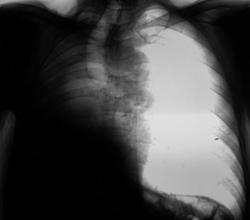

Правосторонний экссудативный плеврит.